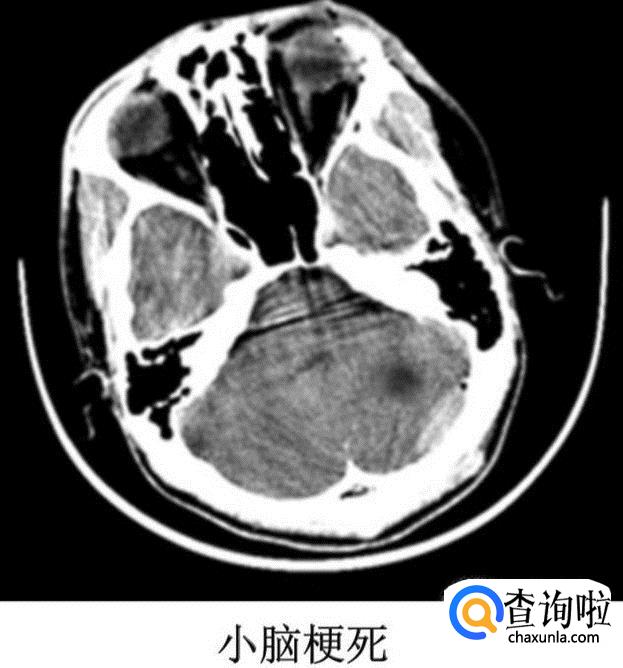

② 小脑梗死

③ 脑干梗死